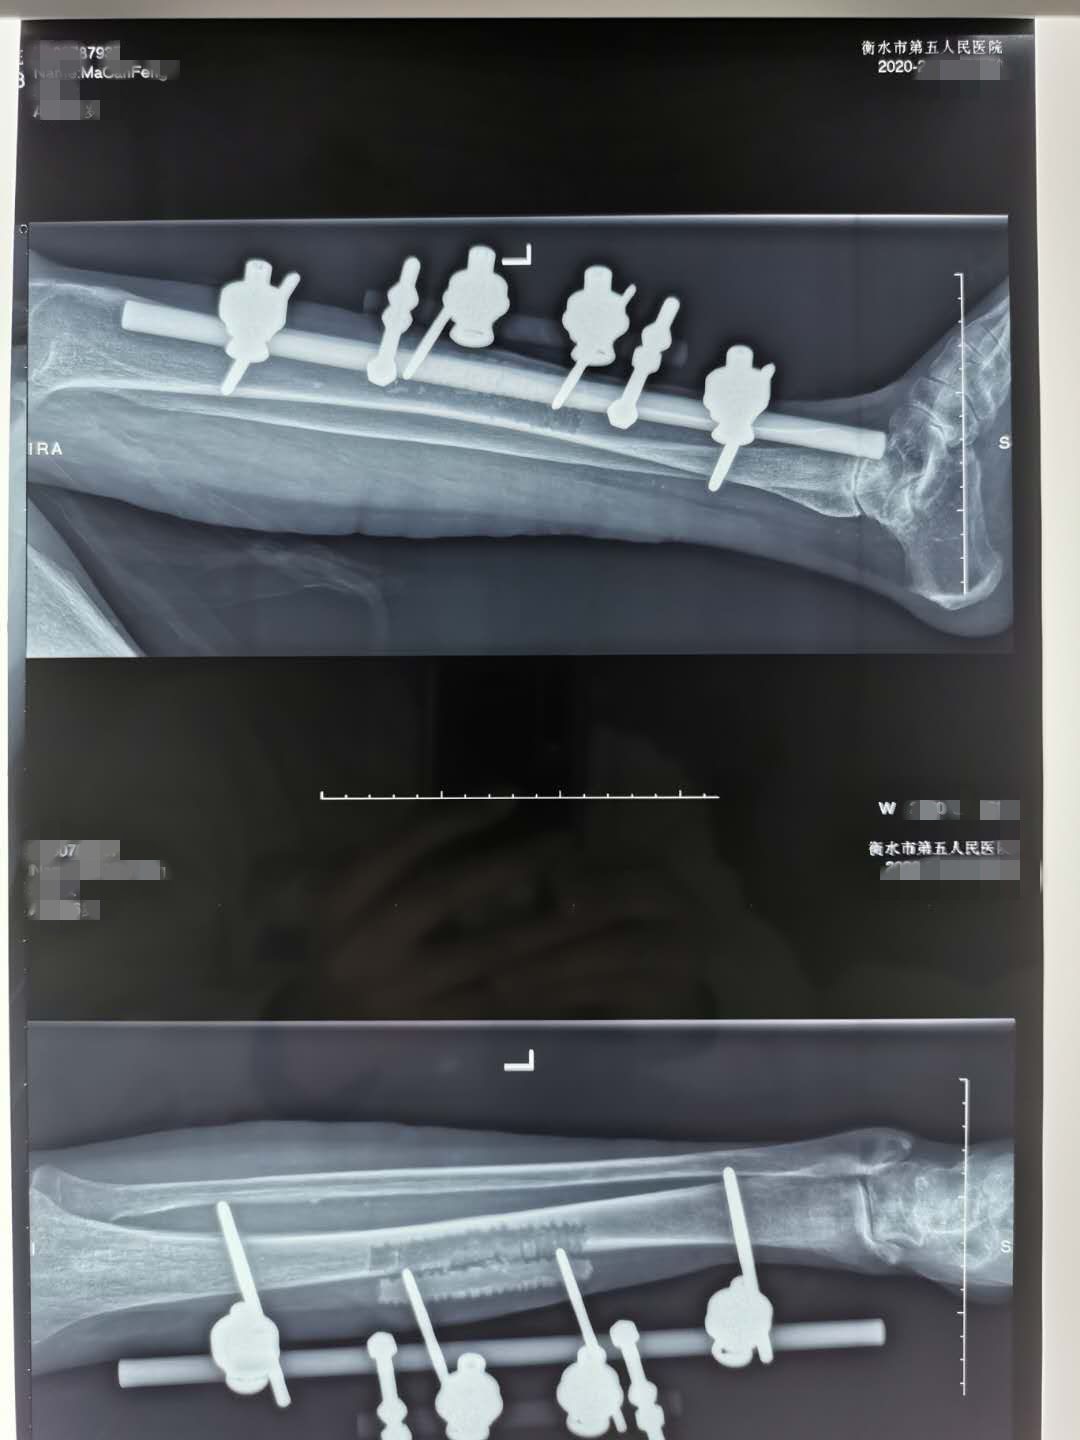

術(shù)中照片

完善術(shù)前準(zhǔn)備后行左脛骨橫向骨搬移術(shù),手術(shù)順利,術(shù)后第5天開始調(diào)整外架向外牽引脛骨骨皮質(zhì),并開始下地活動(dòng)。術(shù)后第8天患者左足疼痛明顯減輕,第10天患者在不應(yīng)用任何止疼藥的情況下疼痛完全消失,術(shù)后六周予以切除壞死的左足第3、4趾,趾蹼間壞死創(chuàng)面自行愈合,我院成功應(yīng)用了目前最先進(jìn)的“橫向骨搬移技術(shù)”,改善了患者缺血肢體的血供,疼痛緩解了,壞死潰爛的創(chuàng)面愈合了,患者臉上露出了開心的笑容,非常高興,非常滿意!